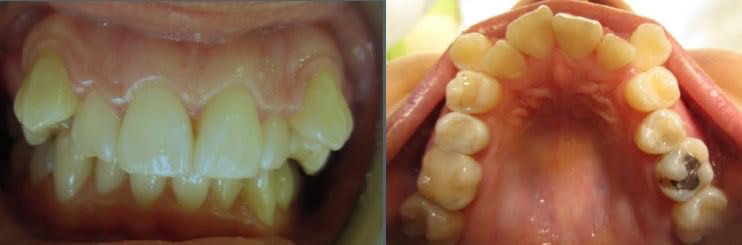

In this case, we were seeing a 28 year old female who wanted her smile improved.

The canines were so way out that the RHS canine actually had no space whatsoever.